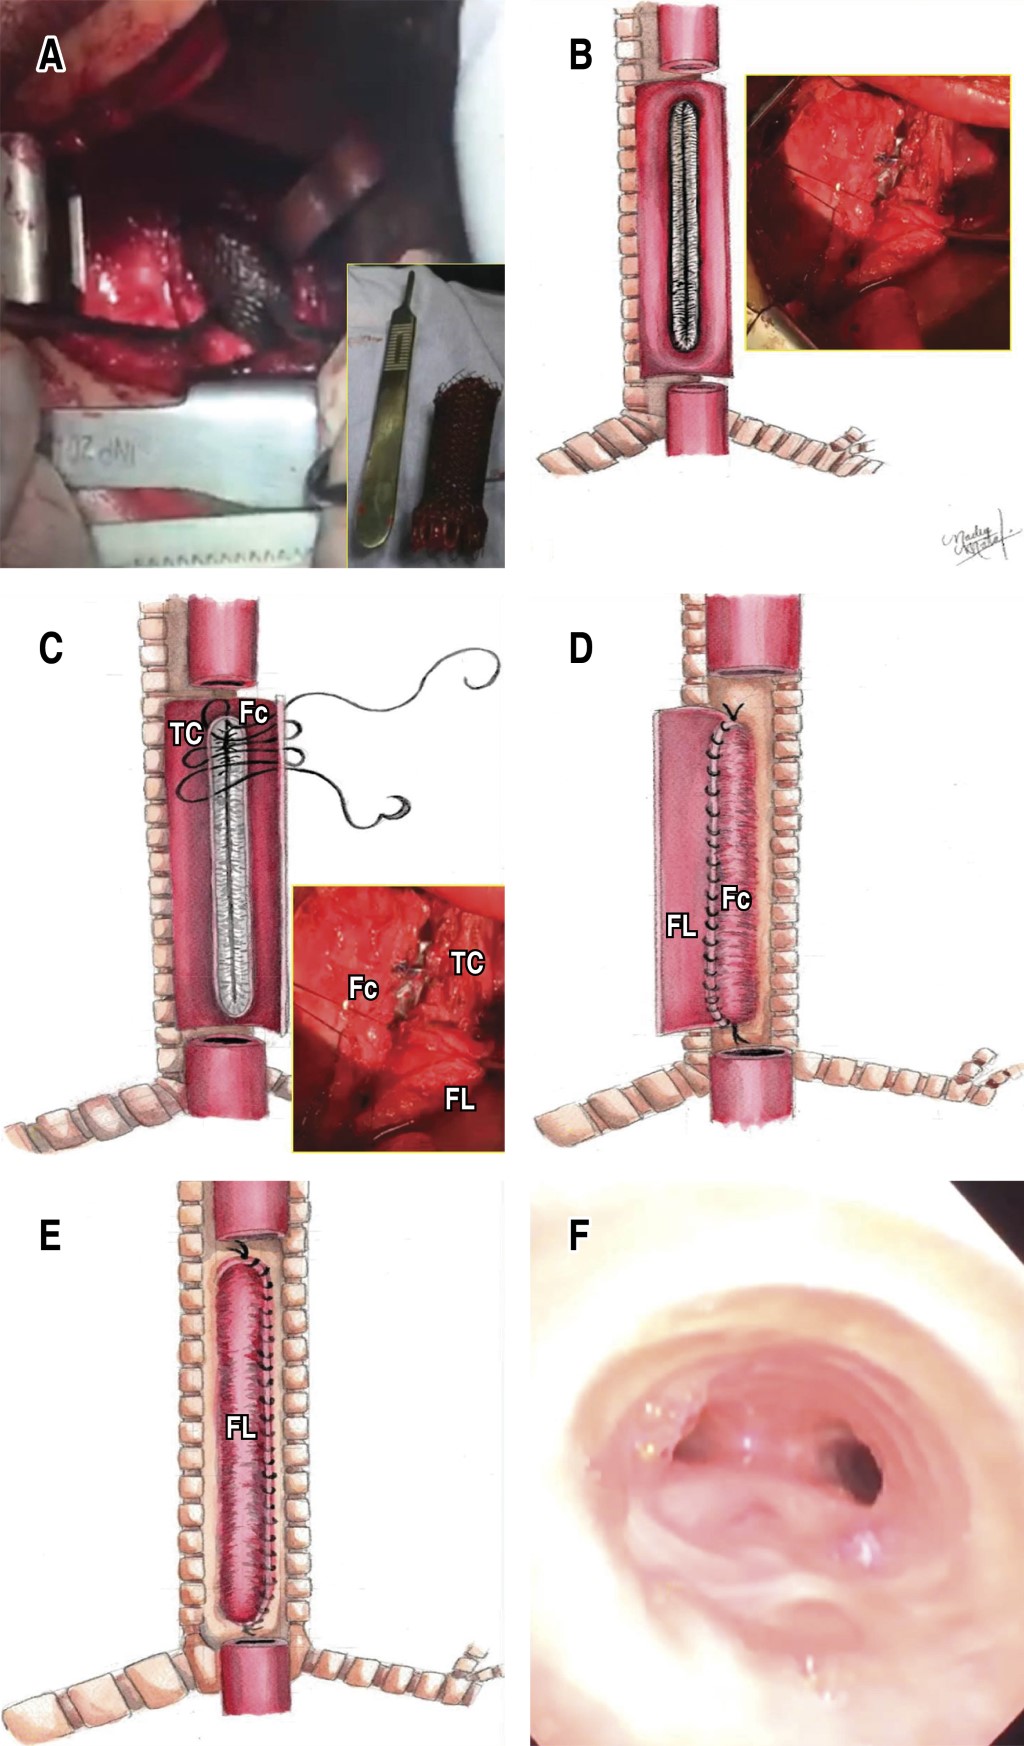

Con intubación endotraqueal inicial guiada por broncoscopia a 1 cm por debajo de la subglotis se realiza toracotomía posterior lateral derecha y se identifica esófago con intensa reacción inflamatoria, se realiza esofagotomía longitudinal, se observa stent intraesofágico, el cual se retira por fragmentos con dificultad por la presencia de adherencias firmes a la parte posterior de la tráquea. Una vez retirada la totalidad del stent, se avanza el tubo endotraqueal hasta 1 cm por arriba de la carina, se ventila al paciente con globo insuflado y se observa una fístula traqueoesofágica en la porción membranosa de la tráquea de 10 cm de largo, el globo insuflado de la cánula endotraqueal permite ocluir la fuga aérea y permite la ventilación mecánica distal. Se revitalizan los bordes del esófago residual y de la tráquea membranosa excluida, la tráquea cartilaginosa anterior se encuentra conservada, se retira mucosa esofágica y se realiza la traqueoplastía membranosa con dos flap o colgajos esofágicos, un flap corto con mucosectomía como primer plano de traqueoplastía membranosa anastomosado al borde cartilaginoso de la tráquea y un posterior colgajo esofágico largo cubriendo en un segundo plano la totalidad de la neotráquea con puntos simples con vicryl 3-0. Se coloca adhesivo tisular hemostático en la superficie de la traqueoplastía y se procede al cierre esofágico distal en cabo ciego y derivación esofágica proximal como esofagostomía cervical; se corrobora adecuado hermetismo de la traqueoplastía sin fuga aérea y con adecuada ventilación por cánula endotraqueal en posición transanastomótica a 1 cm de la carina (Figura 2A-2F).

En la Unidad de Cuidados Críticos se mantiene sedado y con intubación endotraqueal por 72 h y a los seis días posquirúrgicos se realizó una broncoscopia de revisión temprana en donde se observa neotráquea membranosa sin datos de fuga anastomótica y sin complicaciones; se realiza nueva broncoscopia de control a los 20 días de la cirugía en donde existe nuevamente permeabilidad de la neotráquea. Por persistencia de la supuración broncopulmonar se realiza lobectomía inferior izquierda por bronquiectasias a los dos meses posquirúrgicos y a los seis meses método de sustitución esofágica por tubo gástrico reverso retroesternal, evolución clínica, radiológica y endoscópica favorables a cinco años de seguimiento.

El uso de los stent autoexpandibles metálicos esofágicos y de la vía aérea, únicos para las FTEA distales o en combinación para las FTEA mediales y proximales colocados de manera endoscópica se describe en la población adulta como medidas temporales puentes hasta alcanzar una opción quirúrgica definitiva.2,8 En nuestro paciente el stent causante de la FTEA sólo pudo ser retirado de manera transoperatoria para asegurar la vía aeroesofágica, lo cual obligó a una corrección quirúrgica definitiva. Jouraud et al. describieron el uso de la pared esofágica como parche biológico para reconstruir los amplios defectos traqueales inseparables e insuturables.9 La técnica de reconstrucción por traqueoplastía membranosa con doble parche esofágico resulta un método quirúrgico seguro y efectivo al exhibir las siguientes cualidades: a) no requiere la separación de la FTEA evitando lesiones para el nervio laríngeo recurrente; b) la porción esofágica del defecto podría ser usada para una reparación definitiva; c) la porción traqueal del defecto podría ser reparado con el segmento esofágico sin mucosa para brindar estabilidad y rápida recuperación de la neotráquea; d) la técnica de doble parche tiene aporte sanguíneo excelente y brinda soporte y estabilidad ante las presiones altas en la vía aérea; e) la recurrencia posterior a la reconstrucción es muy baja y permitiría el éxito posterior con los métodos endoscópicos; y f) es necesario un método de reconstrucción en la continuidad aerodigestiva, como en nuestro caso, un método de sustitución esofágica y la resección pulmonar posbronquiectasias.6,10